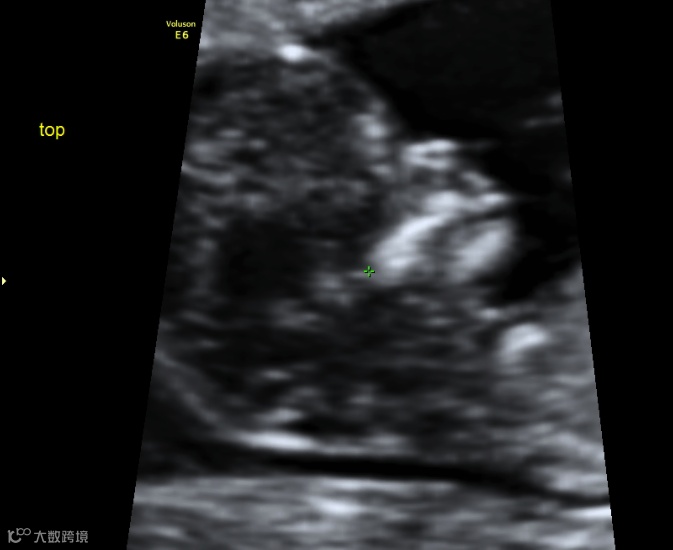

12+周 IVF双胎之一小下颌(对比下图)

12+周 同一病例另一胎下颌正常(对比上图)